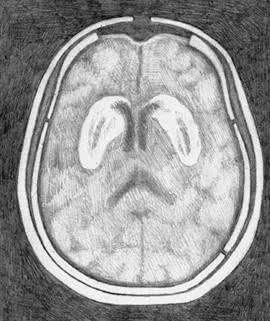

Если, прочитав это, вы почувствовали отчаяние и ужас от мысли, что придется жить без муки и сахара, я хочу заметить, что вот это – голос ваших подавленных дофаминовых рецепторов. Поразительно, насколько сильным может быть это чувство. Кажется, что раз мы отказываемся от этой еды, то в жизни больше не осталось ничего стоящего. Я знаю, как это невыносимо. И вы справитесь, уверяю вас. Дофаминовые рецепторы способны восстанавливаться. И вы снова будете в порядке. Больше чем в порядке – более уверены в себе, свободны от вреда, который эти вещества причиняли вашему мозгу. На рисунке – результаты компьютерной томографии мозга трех разных людей на участке, где в прилежащем ядре располагаются дофаминовые рецепторы. Слева – нормальный мозг, со здоровыми рецепторами, что видно по интенсивности темного участка: чем глубже тень, тем больше неврологическая активность. В центре – снимок мозга человека с кокаиновой зависимостью. Заметьте, что дофаминовый ответ весьма ослаблен. Но посмотрите, справа – мозг человека, страдающего от ожирения. Видите, насколько бледная тень? Дофаминовый ответ еще ниже, чем у человека с кокаиновой зависимостью. Один из ведущих научных принципов заключается в следующем: корреляция не означает причинность. Другими словами, возможно, что не переедание становится причиной истощения дофаминовых рецепторов, а наоборот. Возможно, что мозг человека с ожирением приказывает телу есть так много, потому что его дофаминовые рецепторы изначально были несовершенны. ![]() Нормальный мозг со здоровыми дофаминовыми рецепторами ![]() Мозг человека с кокаиновой зависимостью ![]() Мозг человека, страдающего от ожирения Ученые брали в расчет эту теорию вплоть до мая 2010 года, когда Исследовательский институт Scripps опубликовал статью в журнале «Природа неврологии» (Nature Neuroscience) {46}. Доктор Пол Джонсон и доктор Пол Кенни взяли крыс с нормальным здоровым мозгом и разделили их на две группы. Контрольную группу кормили обычным крысиным кормом. Вторая группа питалась «диетой в стиле кафетерия», включающей в себя бекон, сосиски, чизкейки, бисквиты, глазурь и шоколад, – но только один час в сутки. Третьей группе эта еда была доступна в течение 18–23 часов в день, то есть все, что они могли есть, – пища из «крысиного буфета». Неудивительно, что третью группу постигло ожирение. Но, что более важно, в начале исследования у всех крыс был абсолютно здоровый мозг, в котором впоследствии произошло угнетение дофаминовых рецепторов. Диета в самом деле стала причиной изменений. Наука доказала то, что знает каждый, прошедший через программу «12 шагов»: пищевая зависимость в действительности существует. Она столь же реальна, как кокаиновая. Как героиновая. И с точки зрения физиологии нет никакой разницы. Поначалу исследователи поставили вопрос так: «Итак, еда – это такая же губительная субстанция, как кокаин или героин?» Но сегодня большинство ученых полагают, что речь идет о куда более пагубной зависимости. Пристрастие к сахару и муке В 2007 году в Университете Бордо команда под руководством доктора Сержа Ахмеда вводила крысам кокаин внутривенно до тех пор, пока у животных не выработалась зависимость. Затем грызунам предложили то, чего прежде никогда не давали: сладкую воду. Крыс принудили выбирать между инъекцией кокаина, на котором они уже «сидели», и подслащенной водой. Не имело значения, что использовалось в виде подсластителя, – сахар или его суррогат, – крысы предпочли сладкую воду {47}. Основываясь на этом исследовании, доктор Марк Хайман заявил, что, по его подсчетам, сахар вызывает привыкание в восемь раз сильнее, чем кокаин {48}. В эксперименте, проведенном Исследовательским институтом Scripps, грызуны добровольно перебегали участки пола под напряжением и даже оставались на них, чтобы продолжать есть пищу с высоким содержанием сахара. Степень зависимости можно измерить по силе электротока, который подопытные были готовы выдержать, только бы получить искомое вещество {49}. И степень зависимости у этих крыс достигала порогов кокаиновой или героиновой зависимости. И еще одно наблюдение: когда исследователи переводили крыс с «супераппетитной пищи» на обычный корм, те начинали голодать. Они отказывались есть что-либо, кроме переработанной высококалорийной пищи. Крысы больше не могли потреблять то, что исследователи окрестили «альтернативой салатному меню» {50}. Так откуда нам известно, какая именно пища вызывает зависимость? Некоторые популярные исследования (и исследователи) полагают, что в этом списке сахар, жир и соль {51}. Я не согласна с такой позицией. Во-первых, насколько мне известно, не существует никаких доказательств тому, что соль вызывает привыкание. По правде говоря, с солью еда становится более аппетитной, и мы потребляем больше калорий. В одном эксперименте участники съели на 11 % больше пищи, если она была должным образом посолена {52}. Но аппетитный – это не то же самое, что вызывающий привыкание. |